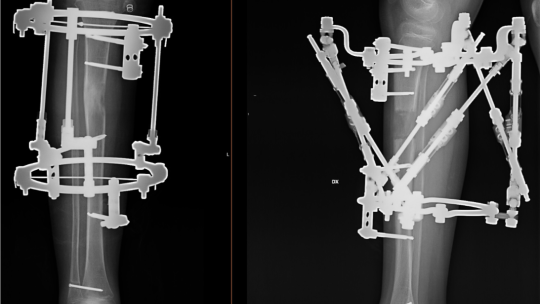

Ekstremitāšu asimetrijas un deformāciju korekcija

Taisnas kājas, viegla gaita, stalta stāja ir ne tikai skaistuma etalons, bet galvenokārt veselības balsts. Ekstremitāšu izliekumam, garumam un simetrijai ir funkcionāla nozīme.